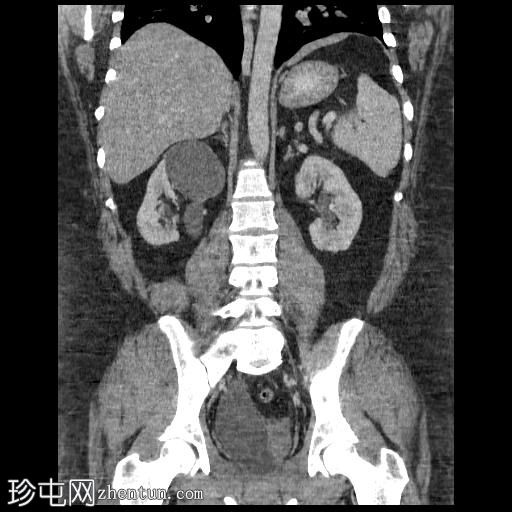

轴位

平扫

右肾集合系统完全重复。上肾集合系统的输尿管异位开口于前列腺尿道,导致上游集合系统显著扩张。这引起肾实质的慢性改变,包括上肾组织变薄和上肾盏排尿功能障碍。

相反,右肾下肾集合系统的输尿管位置正常,无扩张或结石迹象。

左肾和输尿管外观正常。